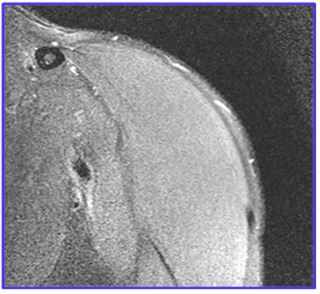

We obtained the higher T2 value in the post-processing image of T2 relaxometry sequence (Figure 2b) at the superior glenohumeral cartilage and were co-related with Figure 2. We used the rainbow scale (Figure 3a & b) in colour map post-processing techniques, where blue indicates higher T2 values and red indicates lower T2 values according to the references [2,3]. The standard T2 relaxometry value of the cartilage is 32.1-35 ms and that in mild and severe osteoarthritic changes of the cartilage is 34.4-41.0 ms and >45 ms, respectively. However, in this case, the T2 values were 45-60 ms (>45 ms) which correlates with the colour maps. Hence, there is an early degeneration of the cartilage (early osteoarthritis) which was difficult to discern in standard greyscale images

Figure 2b: T2 values at the glenohumeral cartilage (45-60ms-inferior to superior in coronal plane).